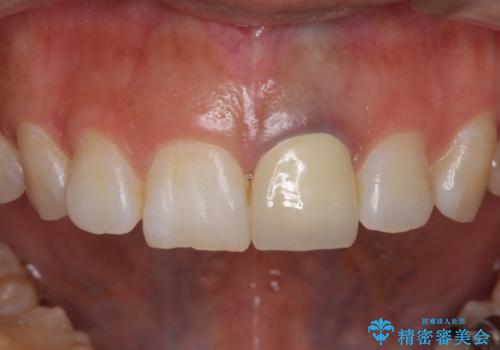

今回は歯自体が黒くなって歯茎から透けて見えている黒ずみのため、セラミック治療で改善させることは困難だというお話をしました。その上でできる範囲できれいに治療することになりました。

今回のように歯自体が金属イオンで黒く変色すると、被せものをメタルフリーにしても黒ずみをすべて隠すのは困難になります。一方、被せものの金属が見えていることが原因の黒ずみの場合は、セラミック治療できれいになりますので、気になる方は一度ご来院ください。